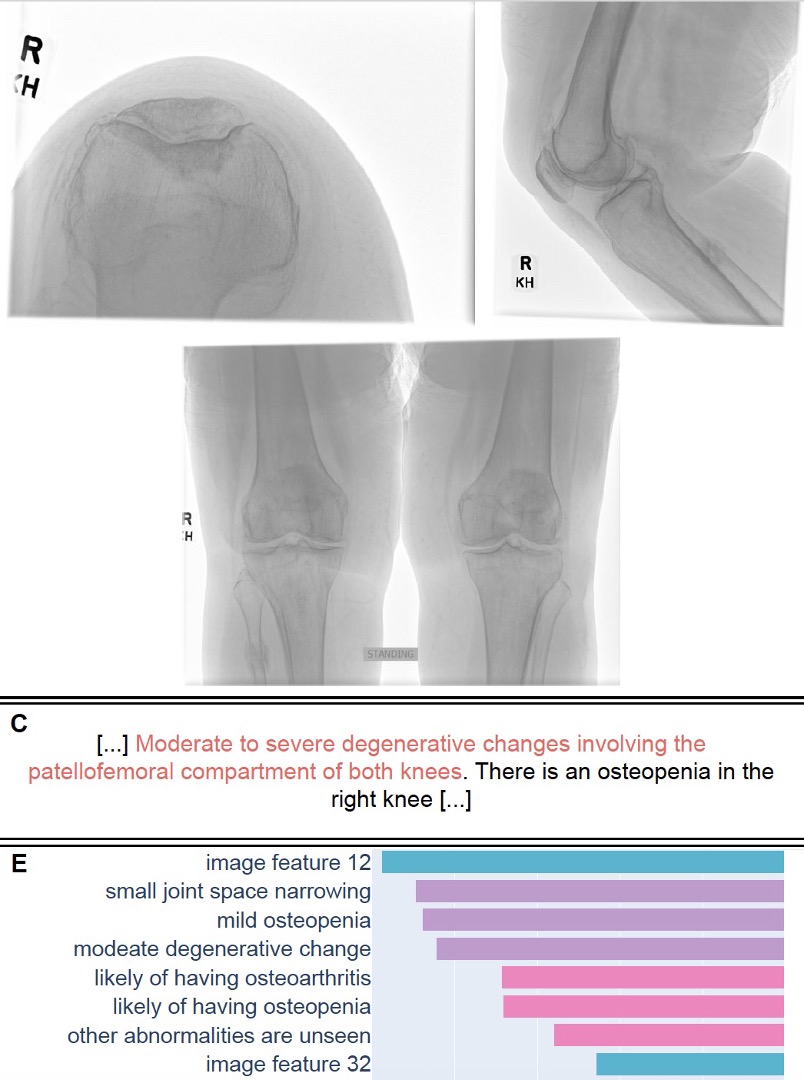

RadGPT, a visual-language AI system enhanced by interactive human-AI refinement, has the potential to aid in the diagnosis and interpretation of knee radiographs MGH Martinos Center Mass General Imaging RSNA #RadAdv Oxford Journals Susanna I Lee doi.org/10.1093/radadv…